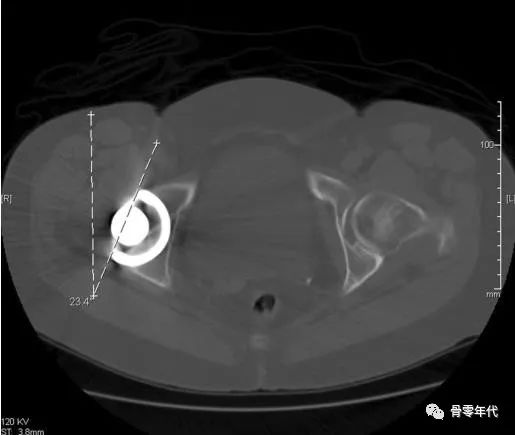

为降低THA术后的脱位率,Lewinnek提出臼杯安全区的概念:影像学前倾角 (15±10°),外展角(40±10°),在安全区内的率为1.5%,在安全区外的脱位率为6.1%,虽有争议但得到大多数学者认可。髋臼前倾角是髋臼开口面与矢状面形成的夹角,臼杯前倾角,即通过在髋关节CT横断面上测量髋臼杯前后壁连线与骨盆矢状轴的夹角。